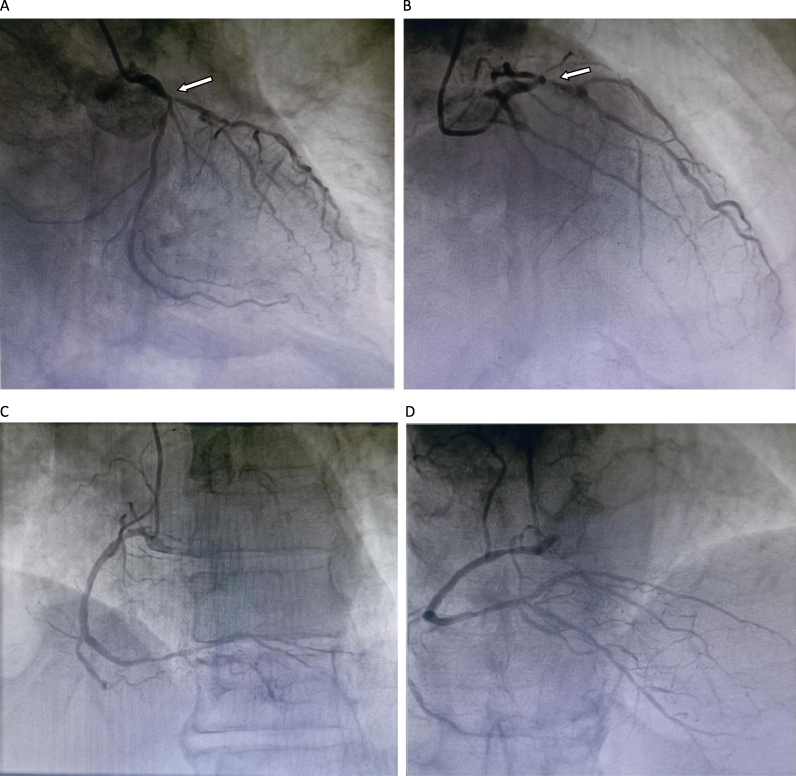

Case presentation: A 65-year old male patient with intermittent chest tightness and shortness of breath for 10 years was admitted for further work-up. On admission, the comprehensive metabolic panel (CMP) revealed a normal liver, kidney and coagulant function, and the BNP, troponin and CK-MB were within the normal limits. ECG showed a sinus rhythm. Cardiac catheterization revealed a three-vessel disease of CAD. Incidentally, echocardiography and MRI found a mobile mass, highly suspicious of cardiac myxomas on the imaging, at the left atrium. A coronary artery bypass grafting (CABG) combining with a right-atrium approach resection of the lesion were devised and concomitantly performed. No surgical complications and major cardiac adverse events occurred post-procedure. After anti-infection and supportive care, the patient recovered uneventfully. Follow-up at 6 months revealed no discomfort of the patient.